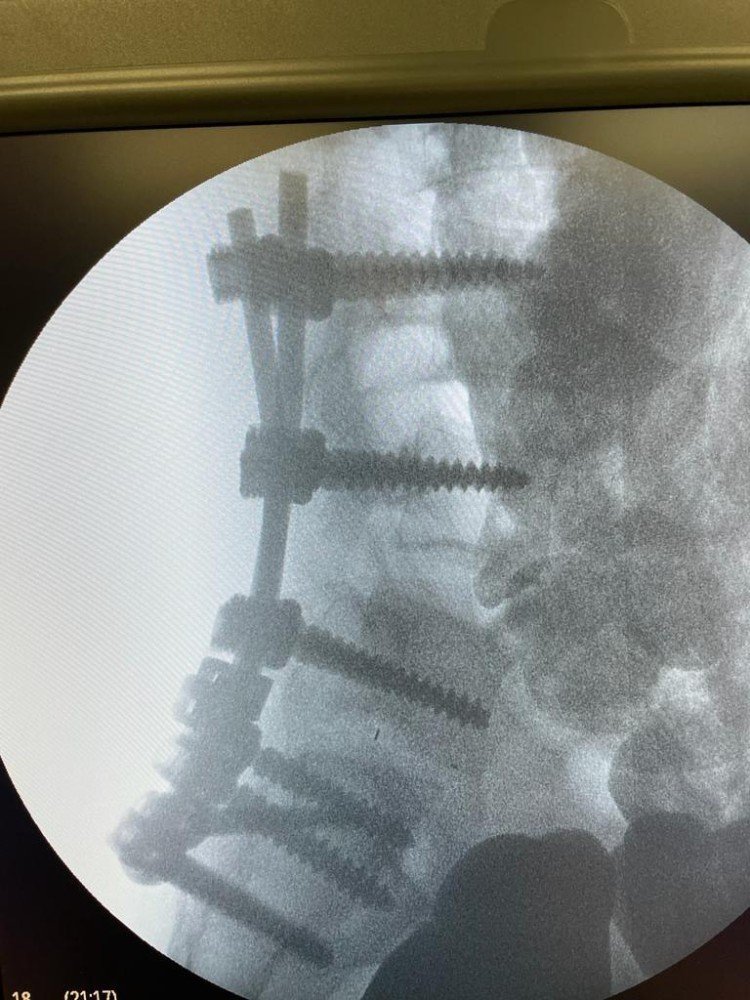

Успешное операционное вмешательство на позвоночник, нейрохирургов травматологического отделения Жуковской ГКБ под руководством кандидата медицинских наук Фыкри Амина Ибрагимовича, позволило двадцатилетнему парню снова встать на ноги. По оценки некоторых специалистов подобная операция уникальна даже в мировом масштабе.

Команда нейрохирургов Жуковской ГКБ в составе: Фыкри Амина, Романова Константина, Тимофея Сергиенко, Андрея Тарасова, Вахтанга Аношина - провела операцию по декомпрессия позвоночного канала и в буквальном смысле, собрала позвоночник заново, укрепив его металлическими конструкциями.